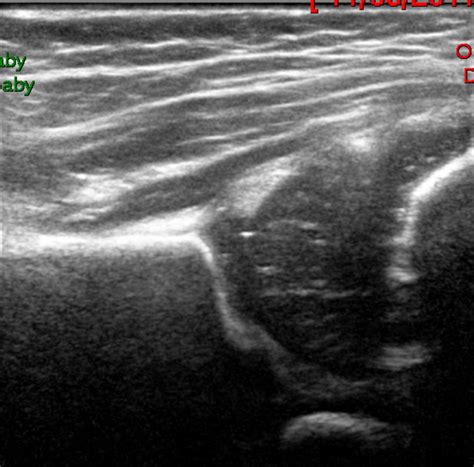

The results of an Infant Hip Ultrasound are interpreted by a radiologist or orthopedic specialist who is trained in pediatric imaging. The images are evaluated for several key factors, including:

• The shape and depth of the acetabulum

• The position of the femoral head within the acetabulum

• The presence of any abnormalities or dislocations